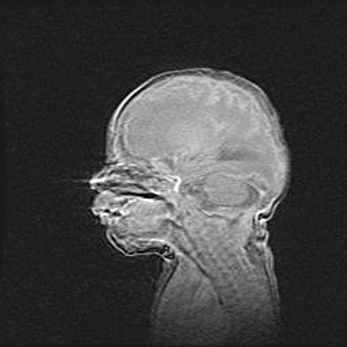

Неполная лизэнцефалия (пахигирия). Открытая гидроцефалия.

Возраст: 17 дней

Вес: 3110 г

Пол: мужской

Окружность головы: 33,5 см

Срок гестации: 35-36 недель

Лизэнцефалия—недоразвитие корковой пластинки и мозговых извилин в результате нарушения миграции нейронов коры. Поверхность мозговых полушарий гладкая. Микроскопически выявляется отсутствие нормальных слоев коры и скопление групп нейронов в подкорковом белом веществе.

Пахигирия—уменьшение числа вторичных извилин. В пораженном полушарии нервные клетки образуют толстый недифференцированный слой с неправильно расположенными нервными волокнами и группами гетеротопных клеток. Нервные клетки незрелые. Белое вещество истончено. При этом нередко аномально развит корково-спинномозговой путь.